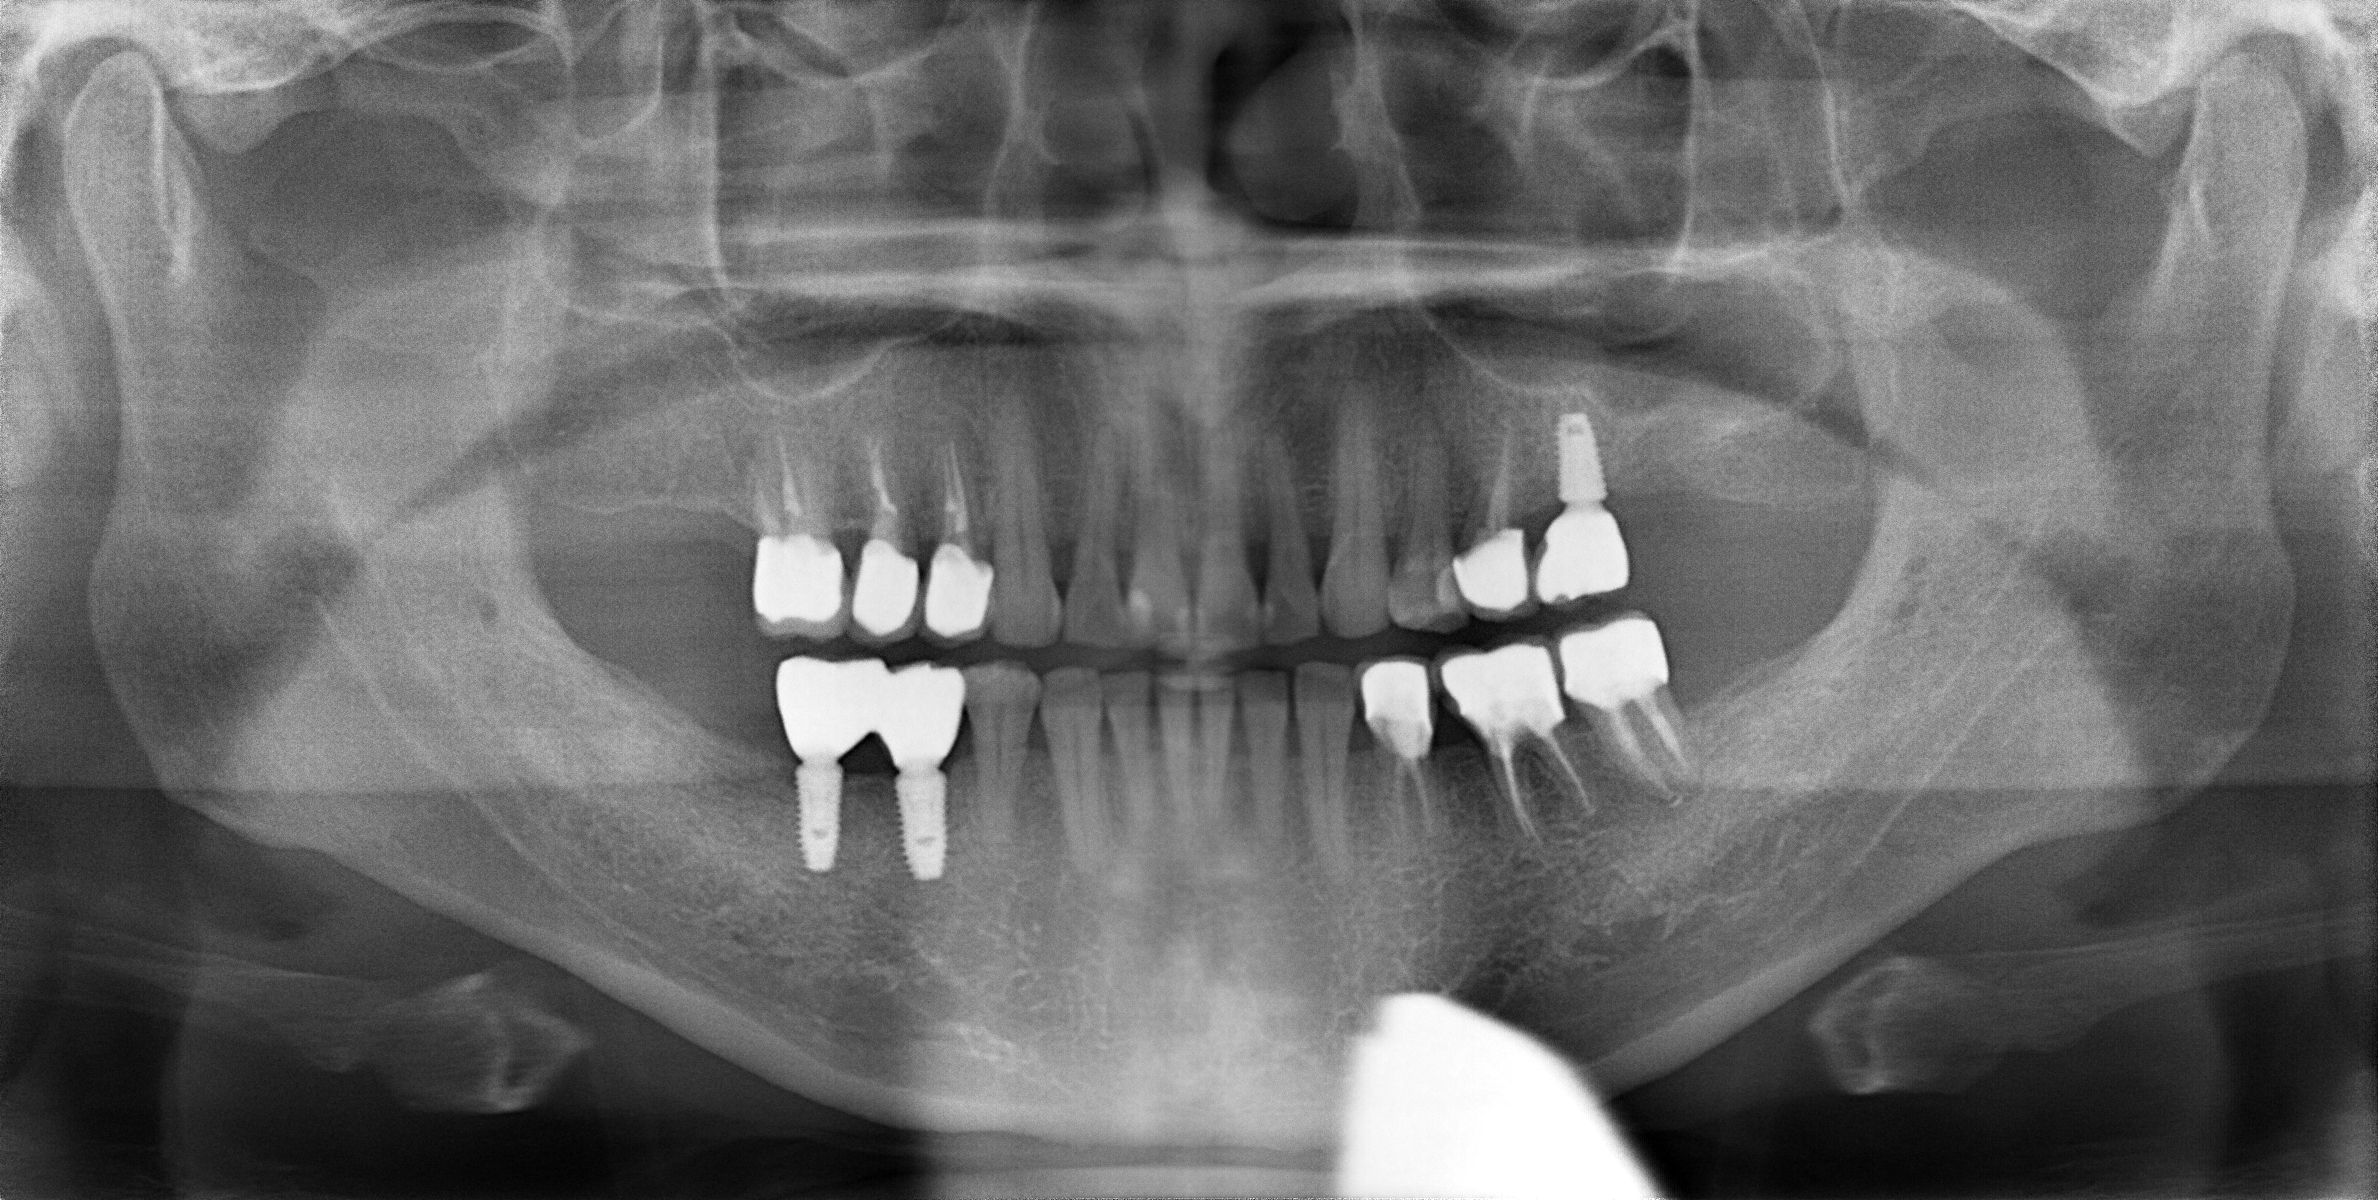

顎関節症の患者さんには、デンタルドック(精密検査)を通して、MRI画像診断とデジタル咬み合わせ検査(T-Scan)を行って治療方針を決定致します。

しかしMRI撮影で軟骨(黄色い矢印)がずれているのを確認していますので、やはり咬み合わせの長期安定を得るのは難しいと思われます。